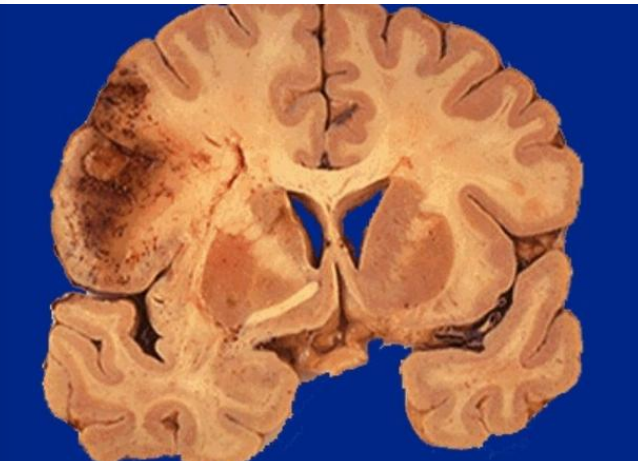

Cerebral infract (early stages)

Cerebral infract